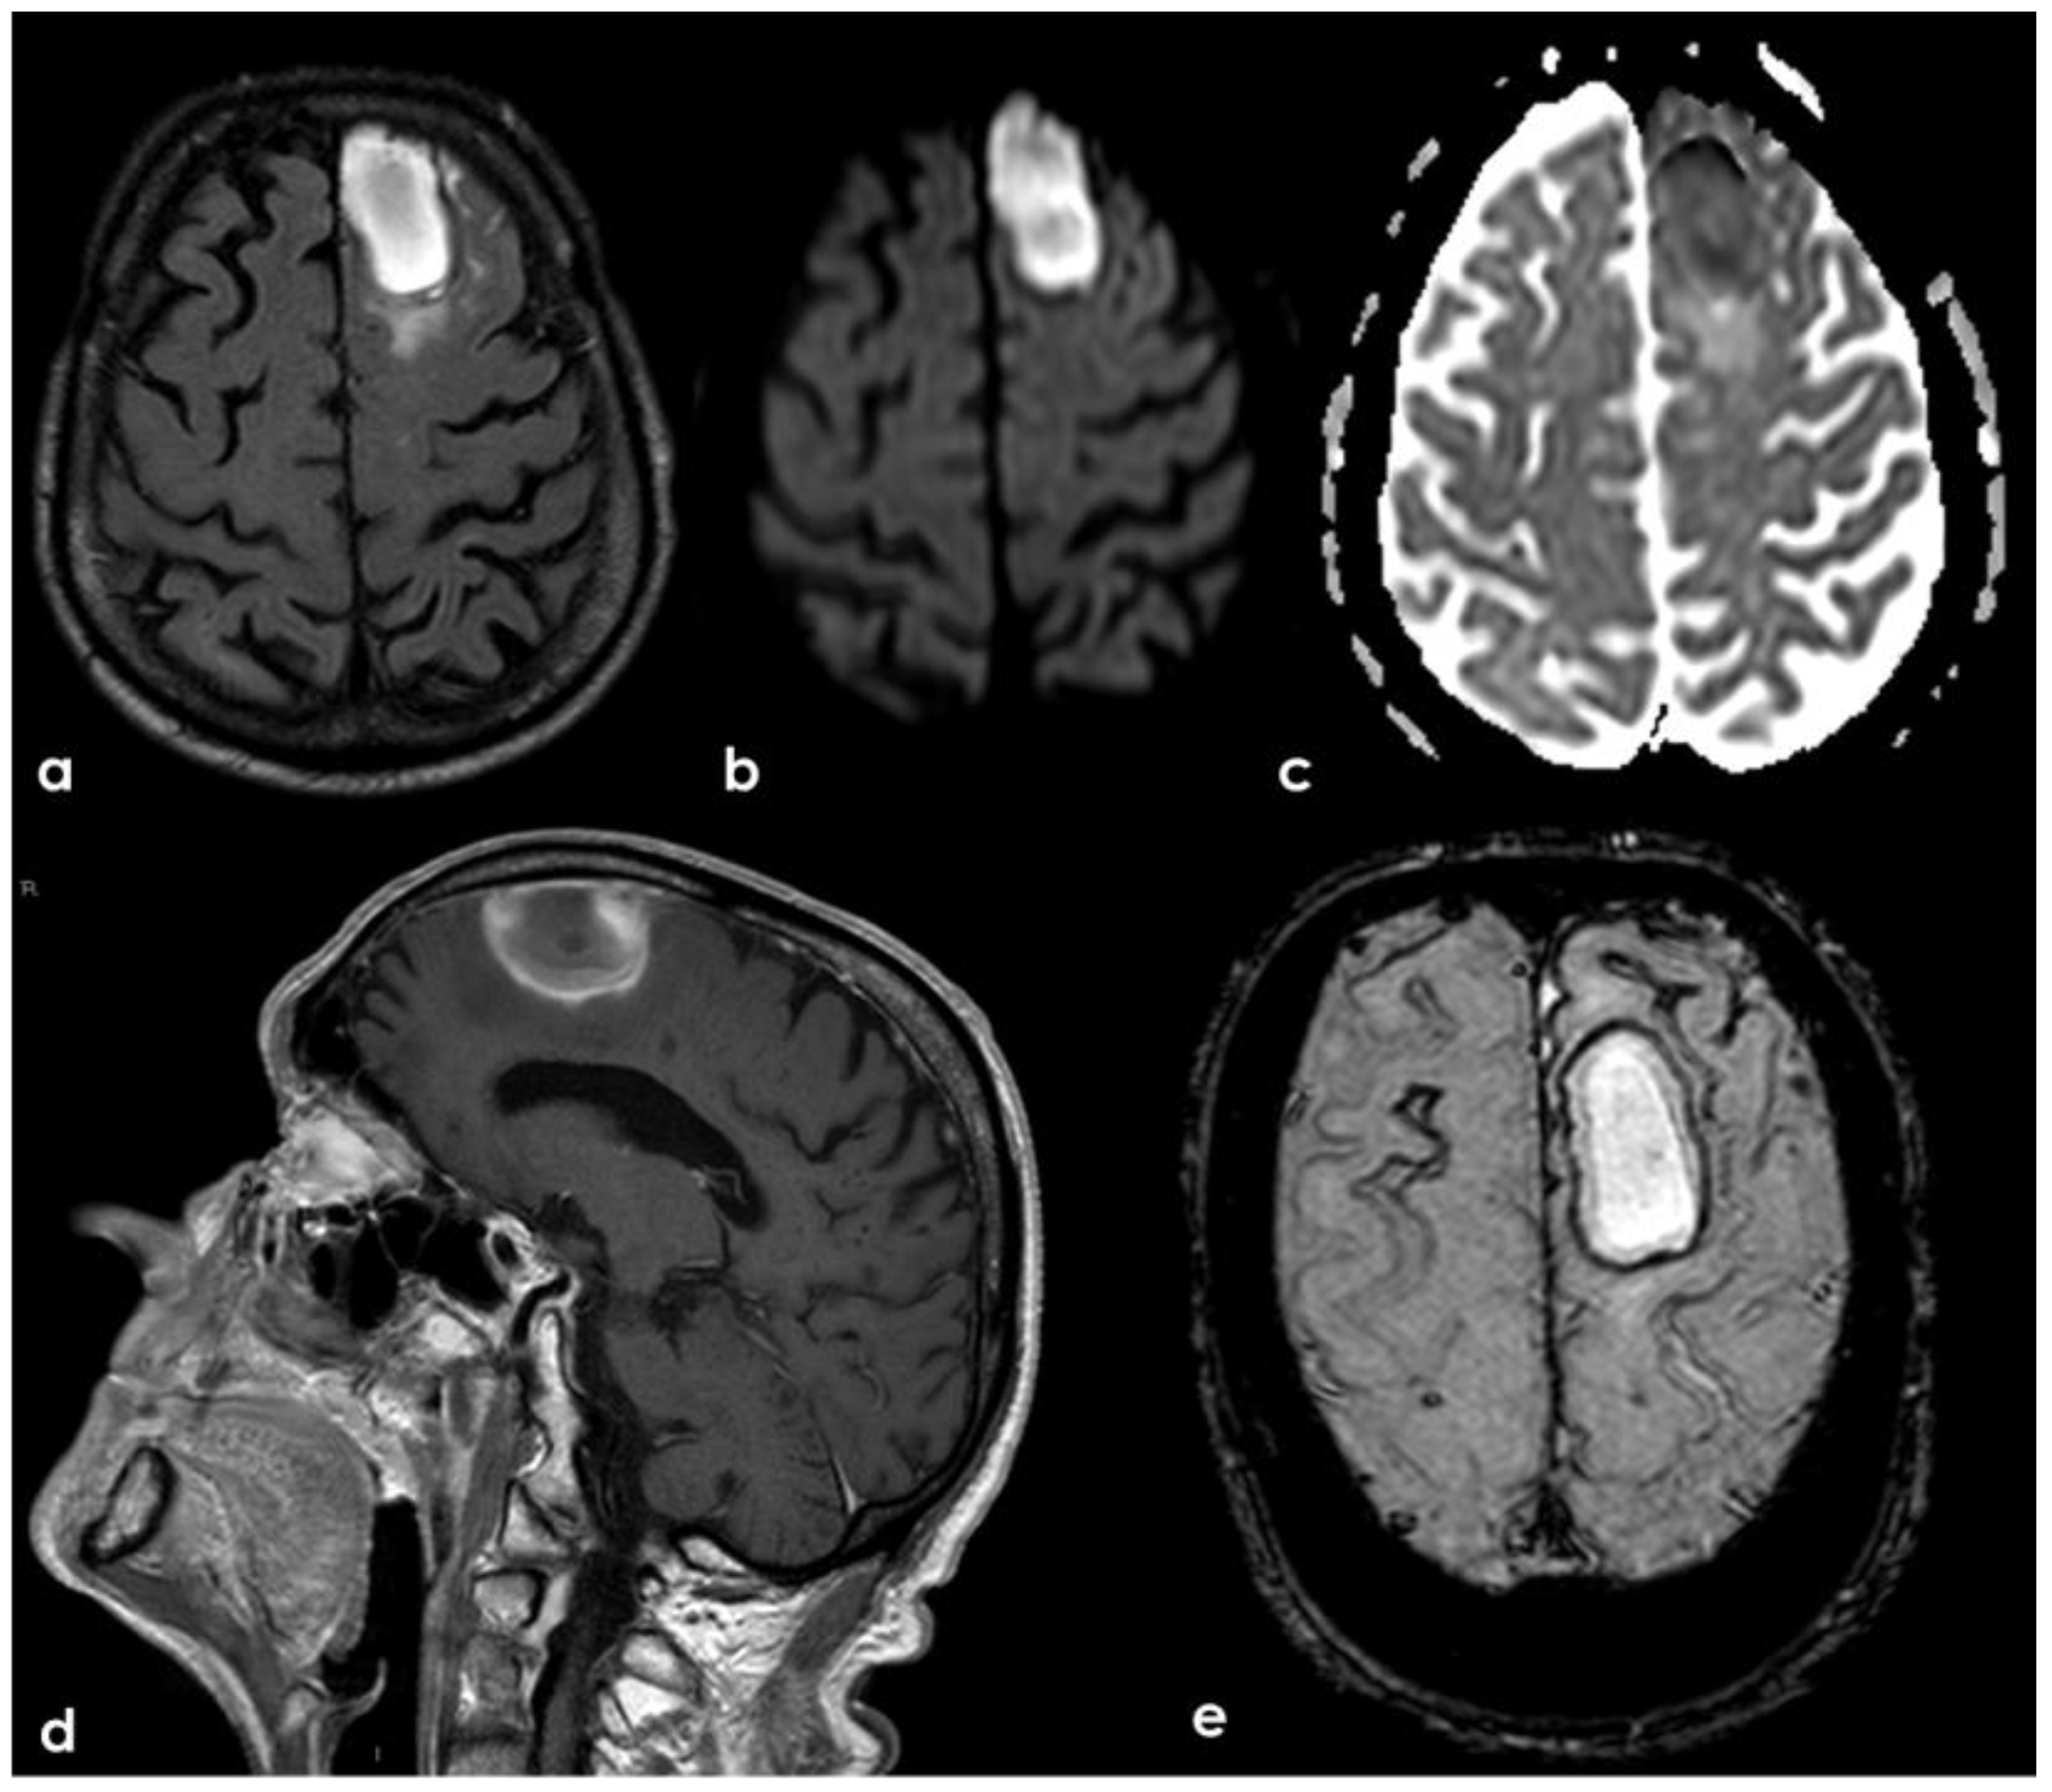

4. December 2015: Ischemic Stroke